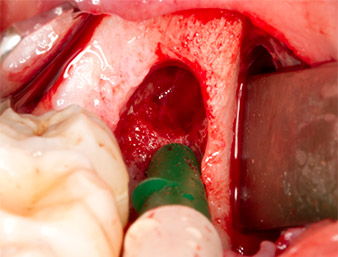

Con el fin de obtener material autógeno para el tratamiento posterior de la herida, se utilizó un inserto piezoquirúrgico (Piezomed B5) para obtener virutas de hueso sano del entorno del resto radicular (figura 5).

El tejido autógeno se extrajo con la punta de trabajo en forma de pala del inserto y se guardó en solución salina fisiológica hasta su posterior utilización (véase figura 13).